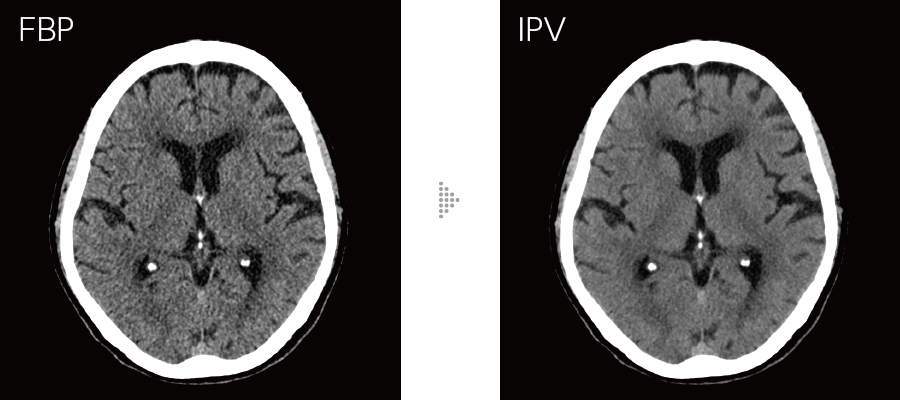

IPVはAI技術*4を活用して開発した画像再構成です。充分な反復処理により得られる画像を教師データとして処理を高速化。富士フイルムが開発したVisual Modelに基づき、RawDataを起点とした画像再構成処理により、NPS(Noise Power Spectrum)をFBP(Filtered Back Projection)に近づけ、高いノイズ低減率においても、画像の質感変化を抑えます。画像ノイズを最大90%*5低減し、被ばく量は最大83%*6低減。低コントラスト検出能を最大2倍*6に改善します。

高周波から低周波まで均等な割合でテクスチャを調整しながら視認性に影響を与えるノイズ周波数特性をFBPに近づけました。